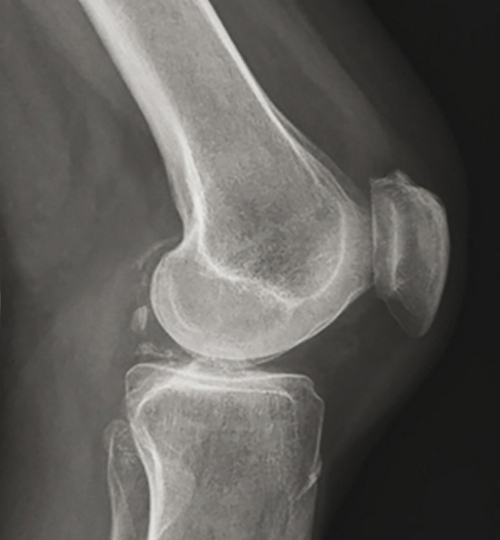

Signes d’arthrose

Lorsque des signes d’arthrose sont décelés dans les premières radiographies (pincement de l’interligne articulaire, ostéophytes, condensation osseuse sous-chondrale, géodes), plusieurs cas de figure existent, en fonction de la clinique :

• Aucune imagerie complémentaire n’est nécessaire s’il s’agit d’un patient de plus de 40 ans, avec un tableau clinique et une évolution typiques (douleurs articulaires liées aux mouvements, raideur matinale absente ou < 30 minutes, résolution de l’épisode douloureux en moins de 10 jours sous traitement symptomatique).

• Une IRM est recommandée pour rechercher une lésion associée (ou scanner ou scintigraphie osseuse en cas de contre-indication à l’IRM) lorsque le tableau clinique est atypique ou les symptômes progressent rapidement de manière inattendue (faisant suspecter une fracture par insuffisance osseuse ou une arthrose destructrice rapide) ou s’il y a un changement des caractéristiques cliniques.

En cas d’échec du traitement symptomatique : orienter vers une prise en charge médico-chirurgicale spécialisée.